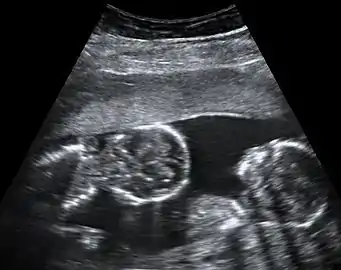

Monozygotic (MZ) or identical twins occur when a single egg is fertilized to form one zygote (hence, "monozygotic") which then divides into two separate embryos. The chances of having identical twins is relatively rare — around 3 or 4 in every 1,000 births.[24]

The degree of separation of the twins in utero depends on if and when they split into two zygotes. Dizygotic twins were always two zygotes. Monozygotic twins split into two zygotes at some time very early in the pregnancy. The timing of this separation determines the chorionicity (the number of placentae) and amniocity (the number of sacs) of the pregnancy. Dichorionic twins either never divided (i.e.: were dizygotic) or they divided within the first 4 days. Monoamnionic twins divide after the first week.

Monochorionic twins generally have two amniotic sacs (called Monochorionic-Diamniotic "MoDi"), which occurs in 60–70% of the pregnancies with monozygotic twins,[46] and in 0.3% of all pregnancies.[48] Monochorionic-Diamniotic twins are almost always monozygotic, with a few exceptions where the blastocysts have fused.[45]

Monochorionic-Monoamniotic Monochorionic twins share the same amnion in 1–2% of monozygotic twin pregnancies.[46]